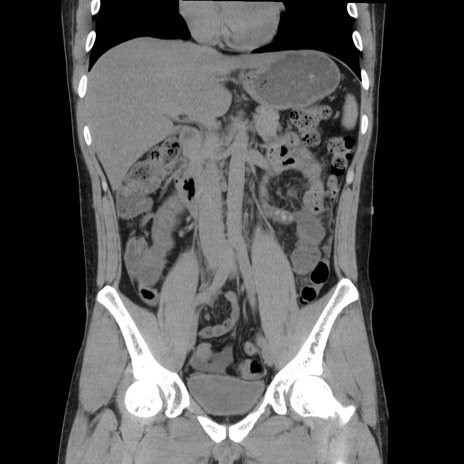

症例36(冠状断像)

【症例】20歳代 男性

【主訴】心窩部痛

【現病歴】今朝より上腹部痛あり。一旦軽快していたが再度出現したため救急要請。昨日夕に白身の魚を含む刺身を食べた。

【身体所見】BP 136/89mmHg、HR 74/min、BT 37.0℃、腹部:膨満、軟、心窩部に圧痛あり。反跳痛なし、筋性防御なし、腸雑音やや亢進あり。

【データ】WBC 17700、CRP 0.48